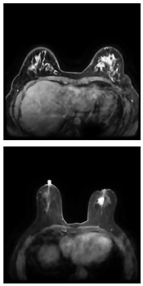

Table 11 presents a comparison between the mask images generated using three different frameworks and the ground truth masks for image segmentation. In Table 12, the performance comparison of various models on the BUSI and BreastDM datasets is presented, emphasizing their respective performance metrics. The methods for calculating performance metrics are detailed in Appendix A.

Table 11.

Comparison of different models using datasets.

For the BUSI dataset, the U-KAN model demonstrates superior performance across most metrics relative to U-Net and U-Net++. Specifically, U-KAN achieves the highest accuracy (0.933), precision (0.754), and F1 score (0.747). Additionally, it records the highest specificity (0.963) and AUC (0.935), although its recall (0.740) is marginally lower than that of U-Net++ (0.749). These results indicate that U-KAN offers balanced and robust performance, excelling particularly in accuracy and specificity, which are critical for reliable image segmentation.

Regarding the BreastDM dataset, all three models exhibit high accuracy, yet U-KAN again shows the best overall performance. U-KAN achieves the highest accuracy (0.986), recall (0.870), F1 score (0.728), specificity (0.993), and AUC (0.838). In comparison, U-Net++ demonstrates slightly lower performance with an accuracy of 0.985 and an AUC of 0.822, while U-Net exhibits an accuracy of 0.983 and an AUC of 0.815.

These findings suggest that U-KAN is particularly effective for image segmentation tasks, especially in the context of early breast cancer diagnosis. It provides superior accuracy, specificity, and balanced performance across other metrics compared to U-Net and U-Net++, thus offering enhanced capabilities for detecting early-stage breast cancer lesions. Consequently, U-KAN’s advanced performance metrics underscore its potential as a reliable model for clinical applications in breast cancer detection.